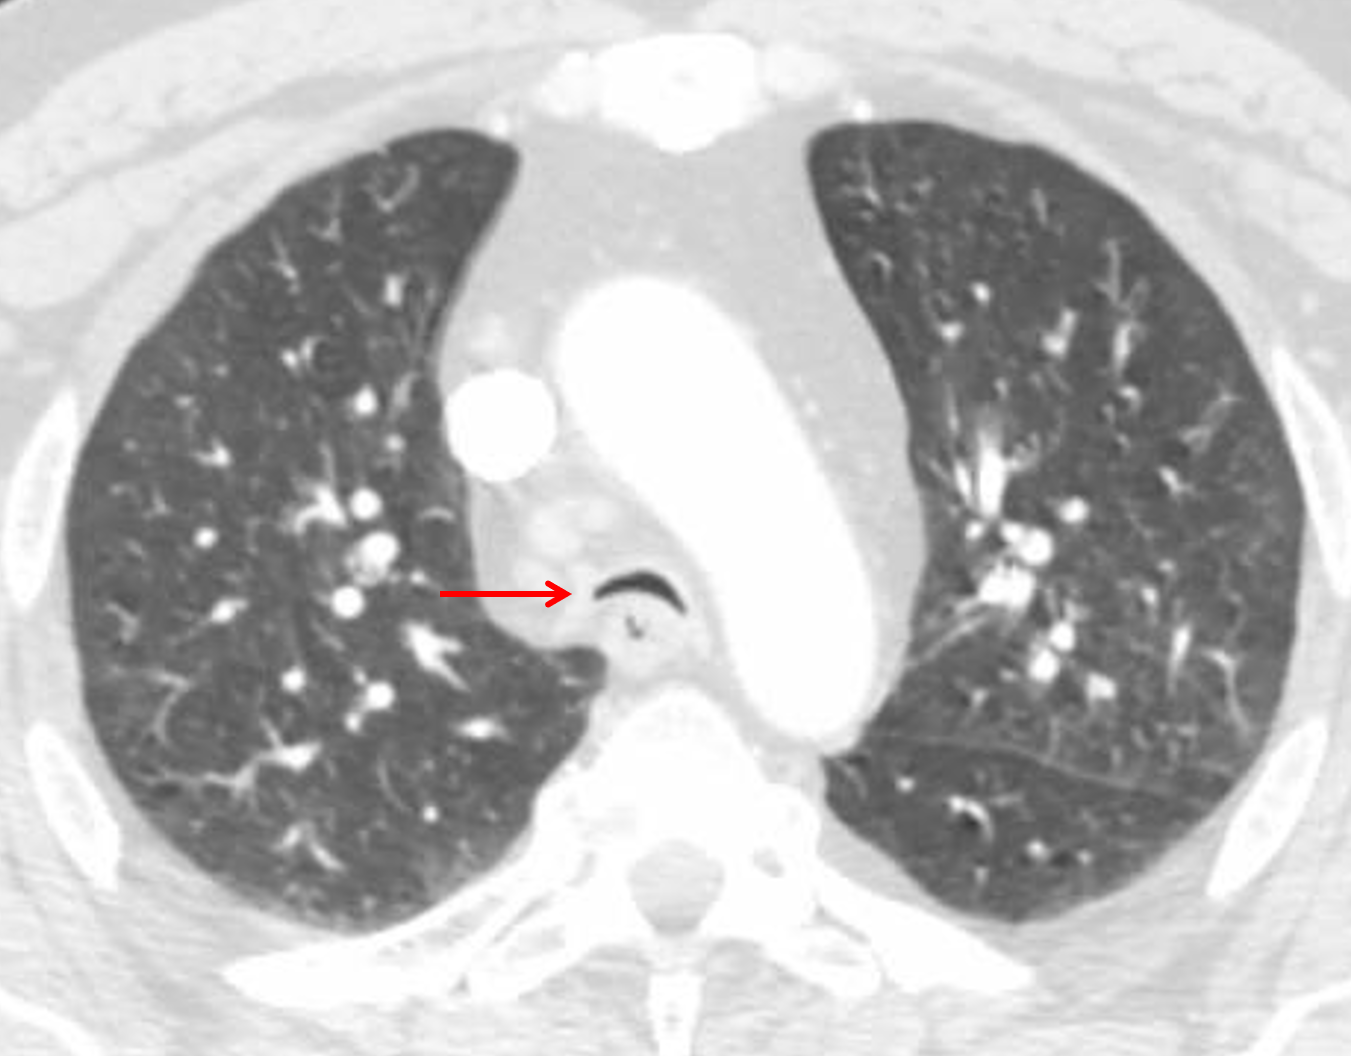

Age: 52

Sex: Male

Indication: Cough

CT

Sample ReportFindings suggestive of infectious or inflammatory bronchitis. No evidence of pneumonia.

Tracheobronchomalacia.

Multiple mildly enlarged mediastinal lymph nodes, which are nonspecific but likely reactive.